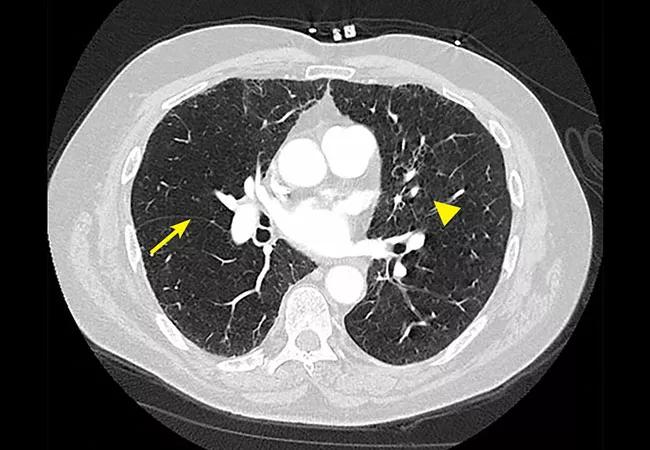

Fissure integrity (a surrogate for absence of collateral ventilation) can be assessed visually or by software analysis on high-resolution CT (Figure 2). Collateral ventilation can be directly investigated with diagnostic tools that can measure pressure and flow within the lung.

Figure 2. Specialized computed tomography software allows objective quantification of fissure integrity. The arrow indicates a complete fissure, and the arrowhead indicates an incomplete fissure. Collateral ventilation is considered highly likely when the fissure is incomplete by > 20% across its span. This is a contraindication to valve therapy.